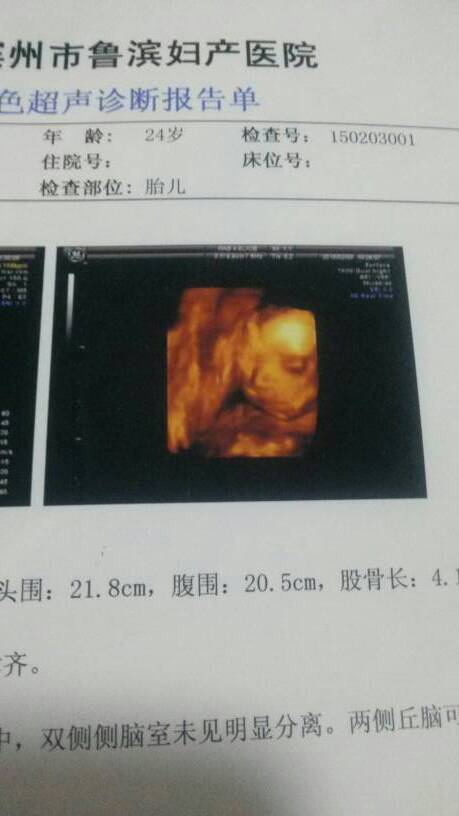

宝妈们看看清楚吗?像男孩女孩啊? 宝妈们看看清楚吗?像男孩女孩啊? 点击展开 睡觉也要美美的 2015-02-11 18:56 为您推荐: 其他回答 看不出来的 ~ S E X 』 2015-02-11 21:36 看不清楚! 小甜猫 2015-02-11 20:42 像男孩,, 馨瑶妈妈 2015-02-11 20:18 就看到个脸,其他都没看到 小乖石头 2015-02-11 19:42 祝宝妈好孕 幸福满满。。添添 2015-02-11 19:13 加载更多 相关问题 看的懂的宝妈们,帮忙看看这是男孩女孩啊 宝妈们看看像男孩女孩呢?怀孕38周加2天了!给点关点奥?谢谢